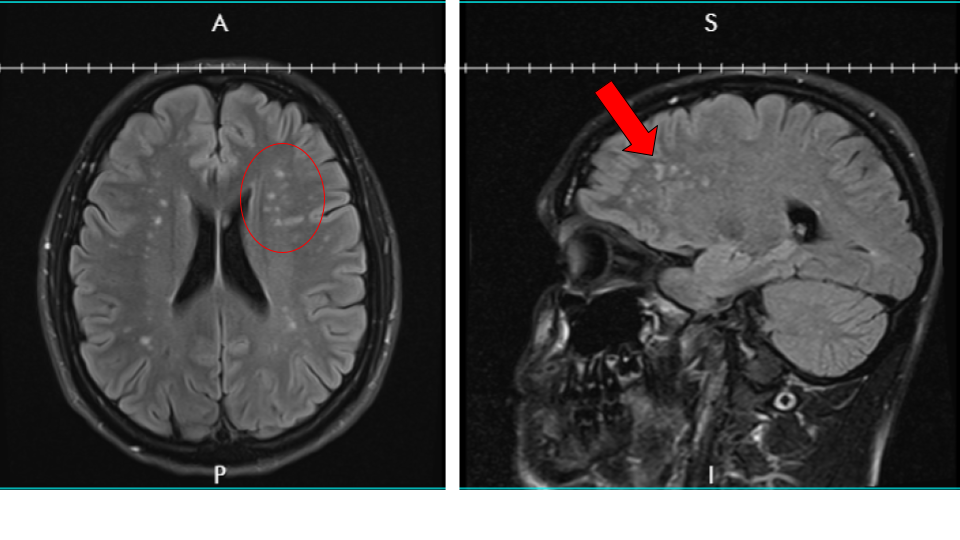

After weeks of trying to get an appointment, I finally saw the doctor and he ordered a bunch of tests including an EEG and an MRI. The EEG was normal. The MRI was not. The MRI revealed that I had lesions on my brain. A lot of them. I had more tests after that including a spinal tap to check for MS but nothing that revealed anything specific. The neuro gave up and said he couldn’t help me so I found a couple more, which took months to schedule.

The white spots on the MRI are known as white matter hyperintensities and are not expected in someone my age

Finally, in October, it looks like we may have finally found the answer to my symptoms. A genetic test revealed a mutation to the COL4A1 gene which produces collagen in the brain. In other words, due to a genetic mutation, my small blood vessels (especially in the brain) are fragile and can break easily. Which means certain areas of my brain weren’t getting enough blood and the cells died, which is what the white spots on the MRI showed and why I had the symptoms I was experiencing. There is no cure, and it’s something that I’m going to have to treat and monitor for the rest of my life.